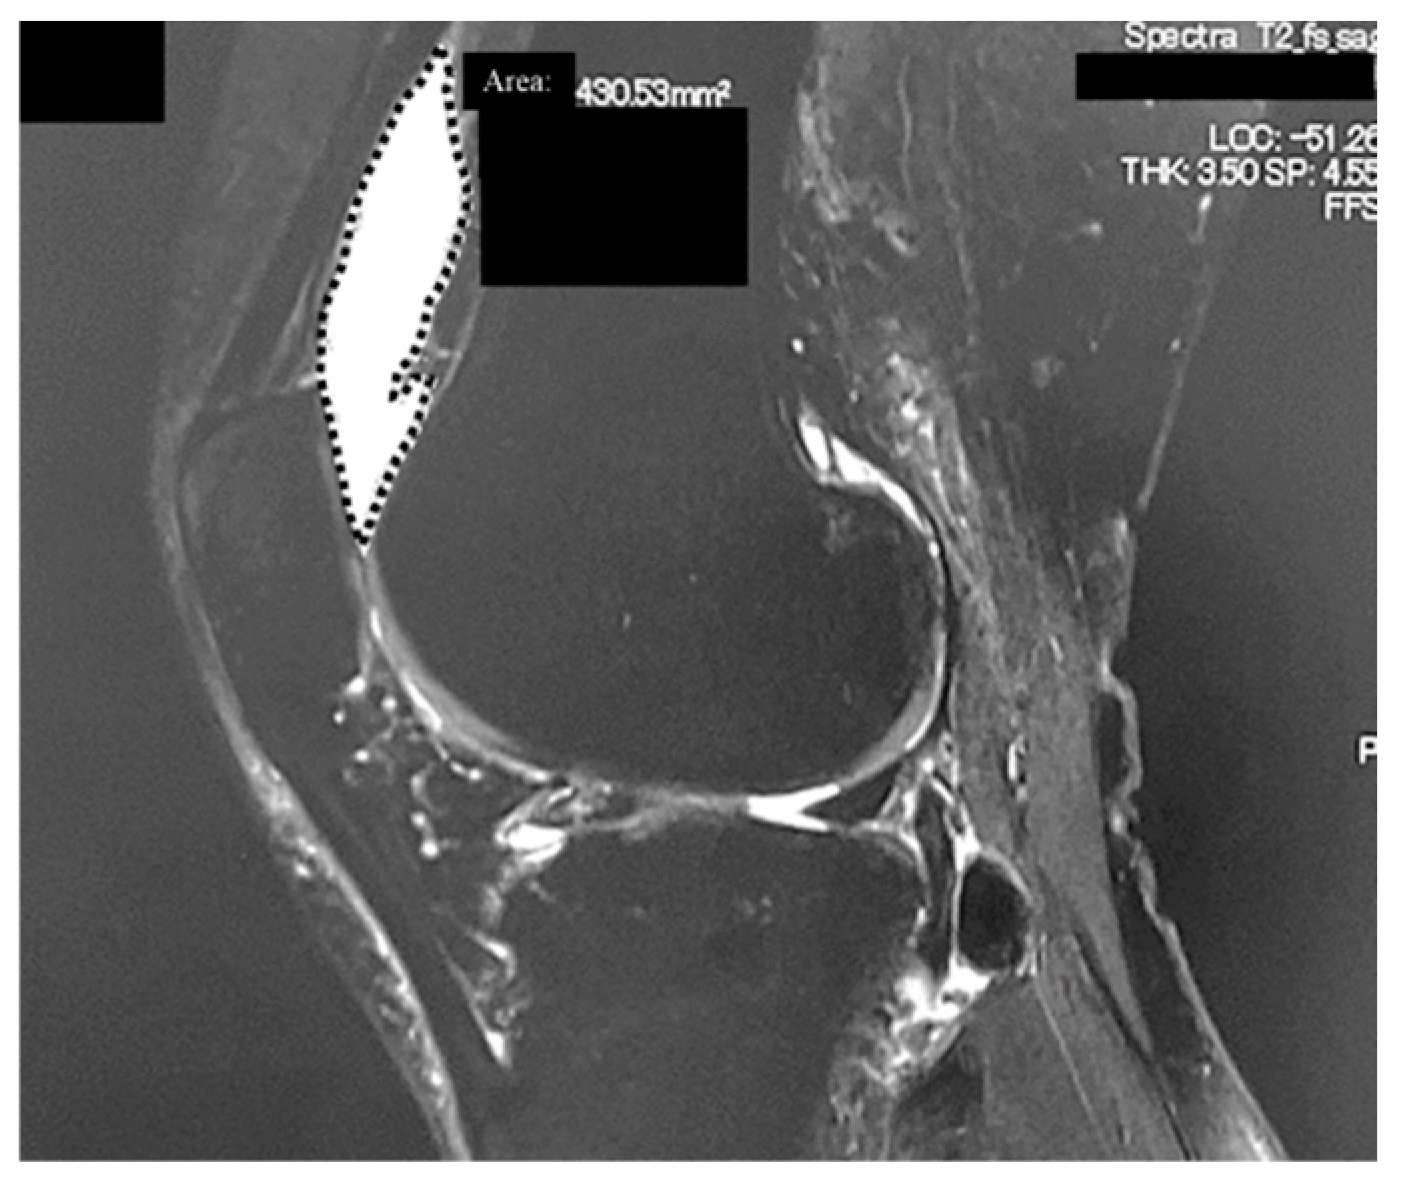

2.2. Radiological Analyses

| Area of synovial fluid (cm2) | KL2 | 1.6 ± 1.3 | 1.2 ± 1.2 | 0.008 |

| KL3 | 2.2 ± 1.7 | 1.8 ± 1.6 | 0.17 | |

| KL4 | 2.3 ± 2.0 | 2.0 ± 1.7 | 0.009 | |

| Total (KL2~4) | 2.1 ± 1.8 | 1.7 ± 1.6 | <0.001 |